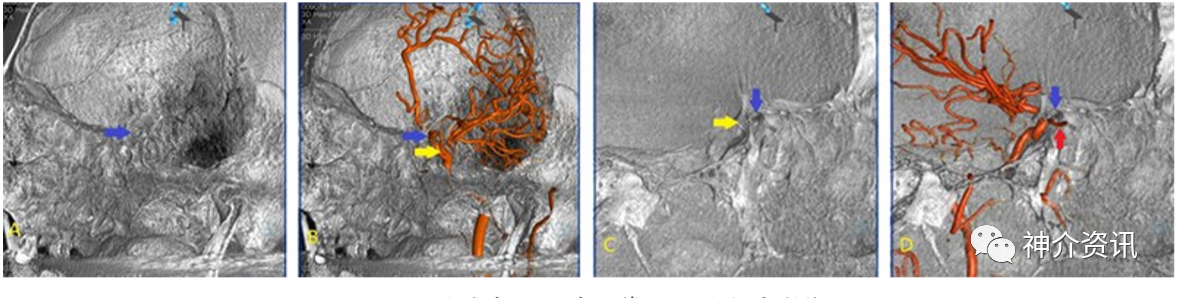

收集100例DSA检查无异常发现的病人,利用其三维脑血管成像及三维颅骨成像数据,在Siemens双C臂机Syngo后处理工作站,进行三维数据融合,获得3D-DSA/3D-CT的融合影像,选择颅眶区手术入路的步骤,对血管影像与颅骨相关及毗邻关系进行观察并测量与手术入路相关的数据,在三维静态(冠状位、矢状位、轴位及与手术相关的角度)与连续动态融合影像模拟手术入路步骤进行操作。

观察发现多数眼动脉起始部位于颈内动脉床突段内侧,沿视神经管外下方走行。颅骨左右径平均(143.89±5.78)mm,颅骨前后径平均(173.14±5.68)mm,双侧眼动脉起始处至视神经管上壁距离平均(7.32±2.42)mm,视神经孔到眶上裂距离平均(2.42±0.69)mm。在三维融合影像中发现2例眼动脉未经视神经管入眶的变异。

颅眶手术入路双容积融合影像,与单一影像相比,可显示手术入路的相互比邻解剖关系,对手术有更精准的参考价值。应用手术对象的融合影像显示手术入路,可达到标准化、个体化,对手术参考价值更大,更符合手术真实情况。